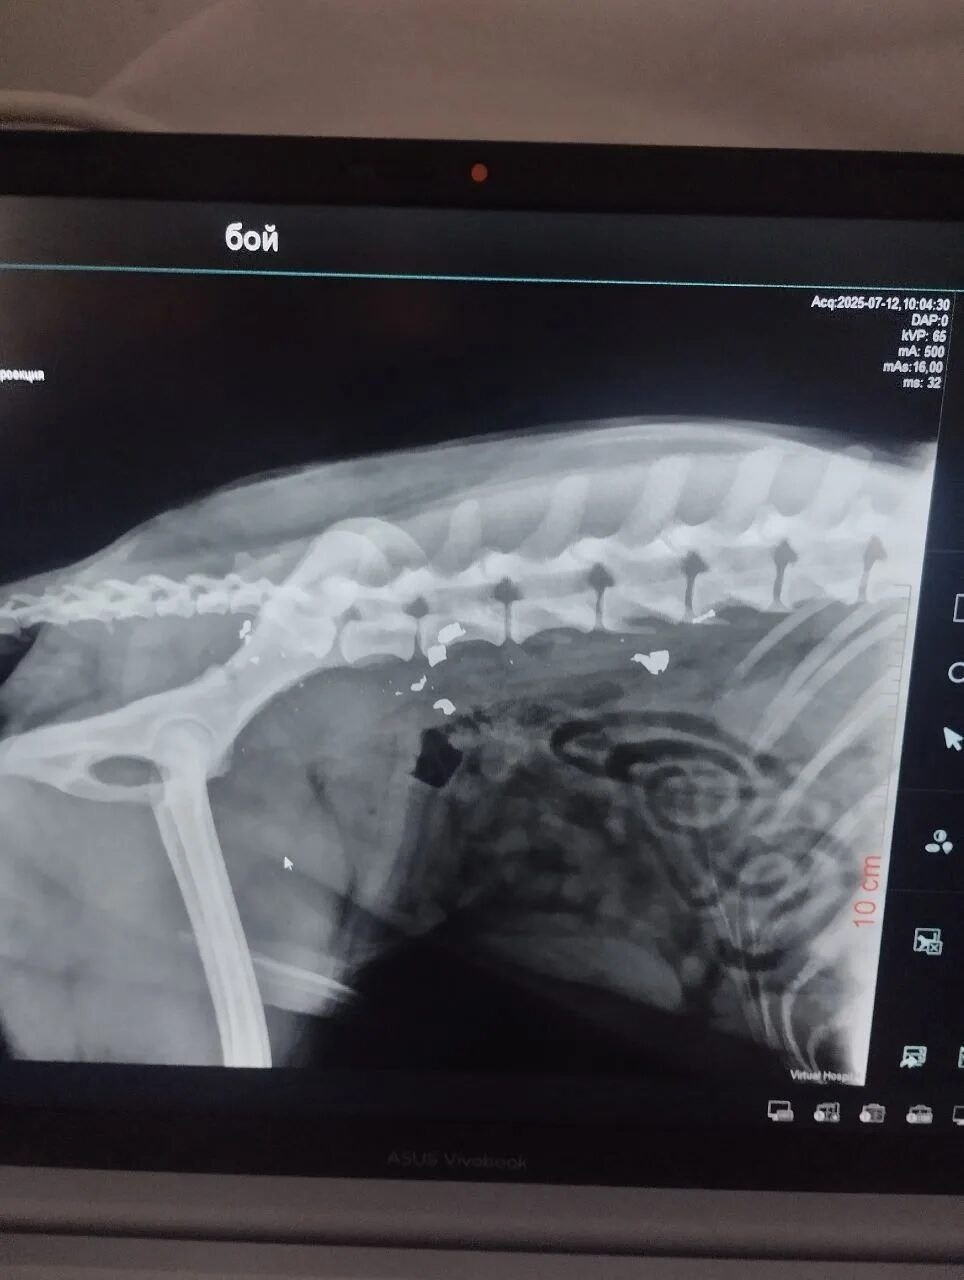

Когда-то Боя уже возили в Волгоград на рентген, но полноценного лечения он не получил и снова оказался на улице. Итог — инвалидность и гниющая заживо конечность.